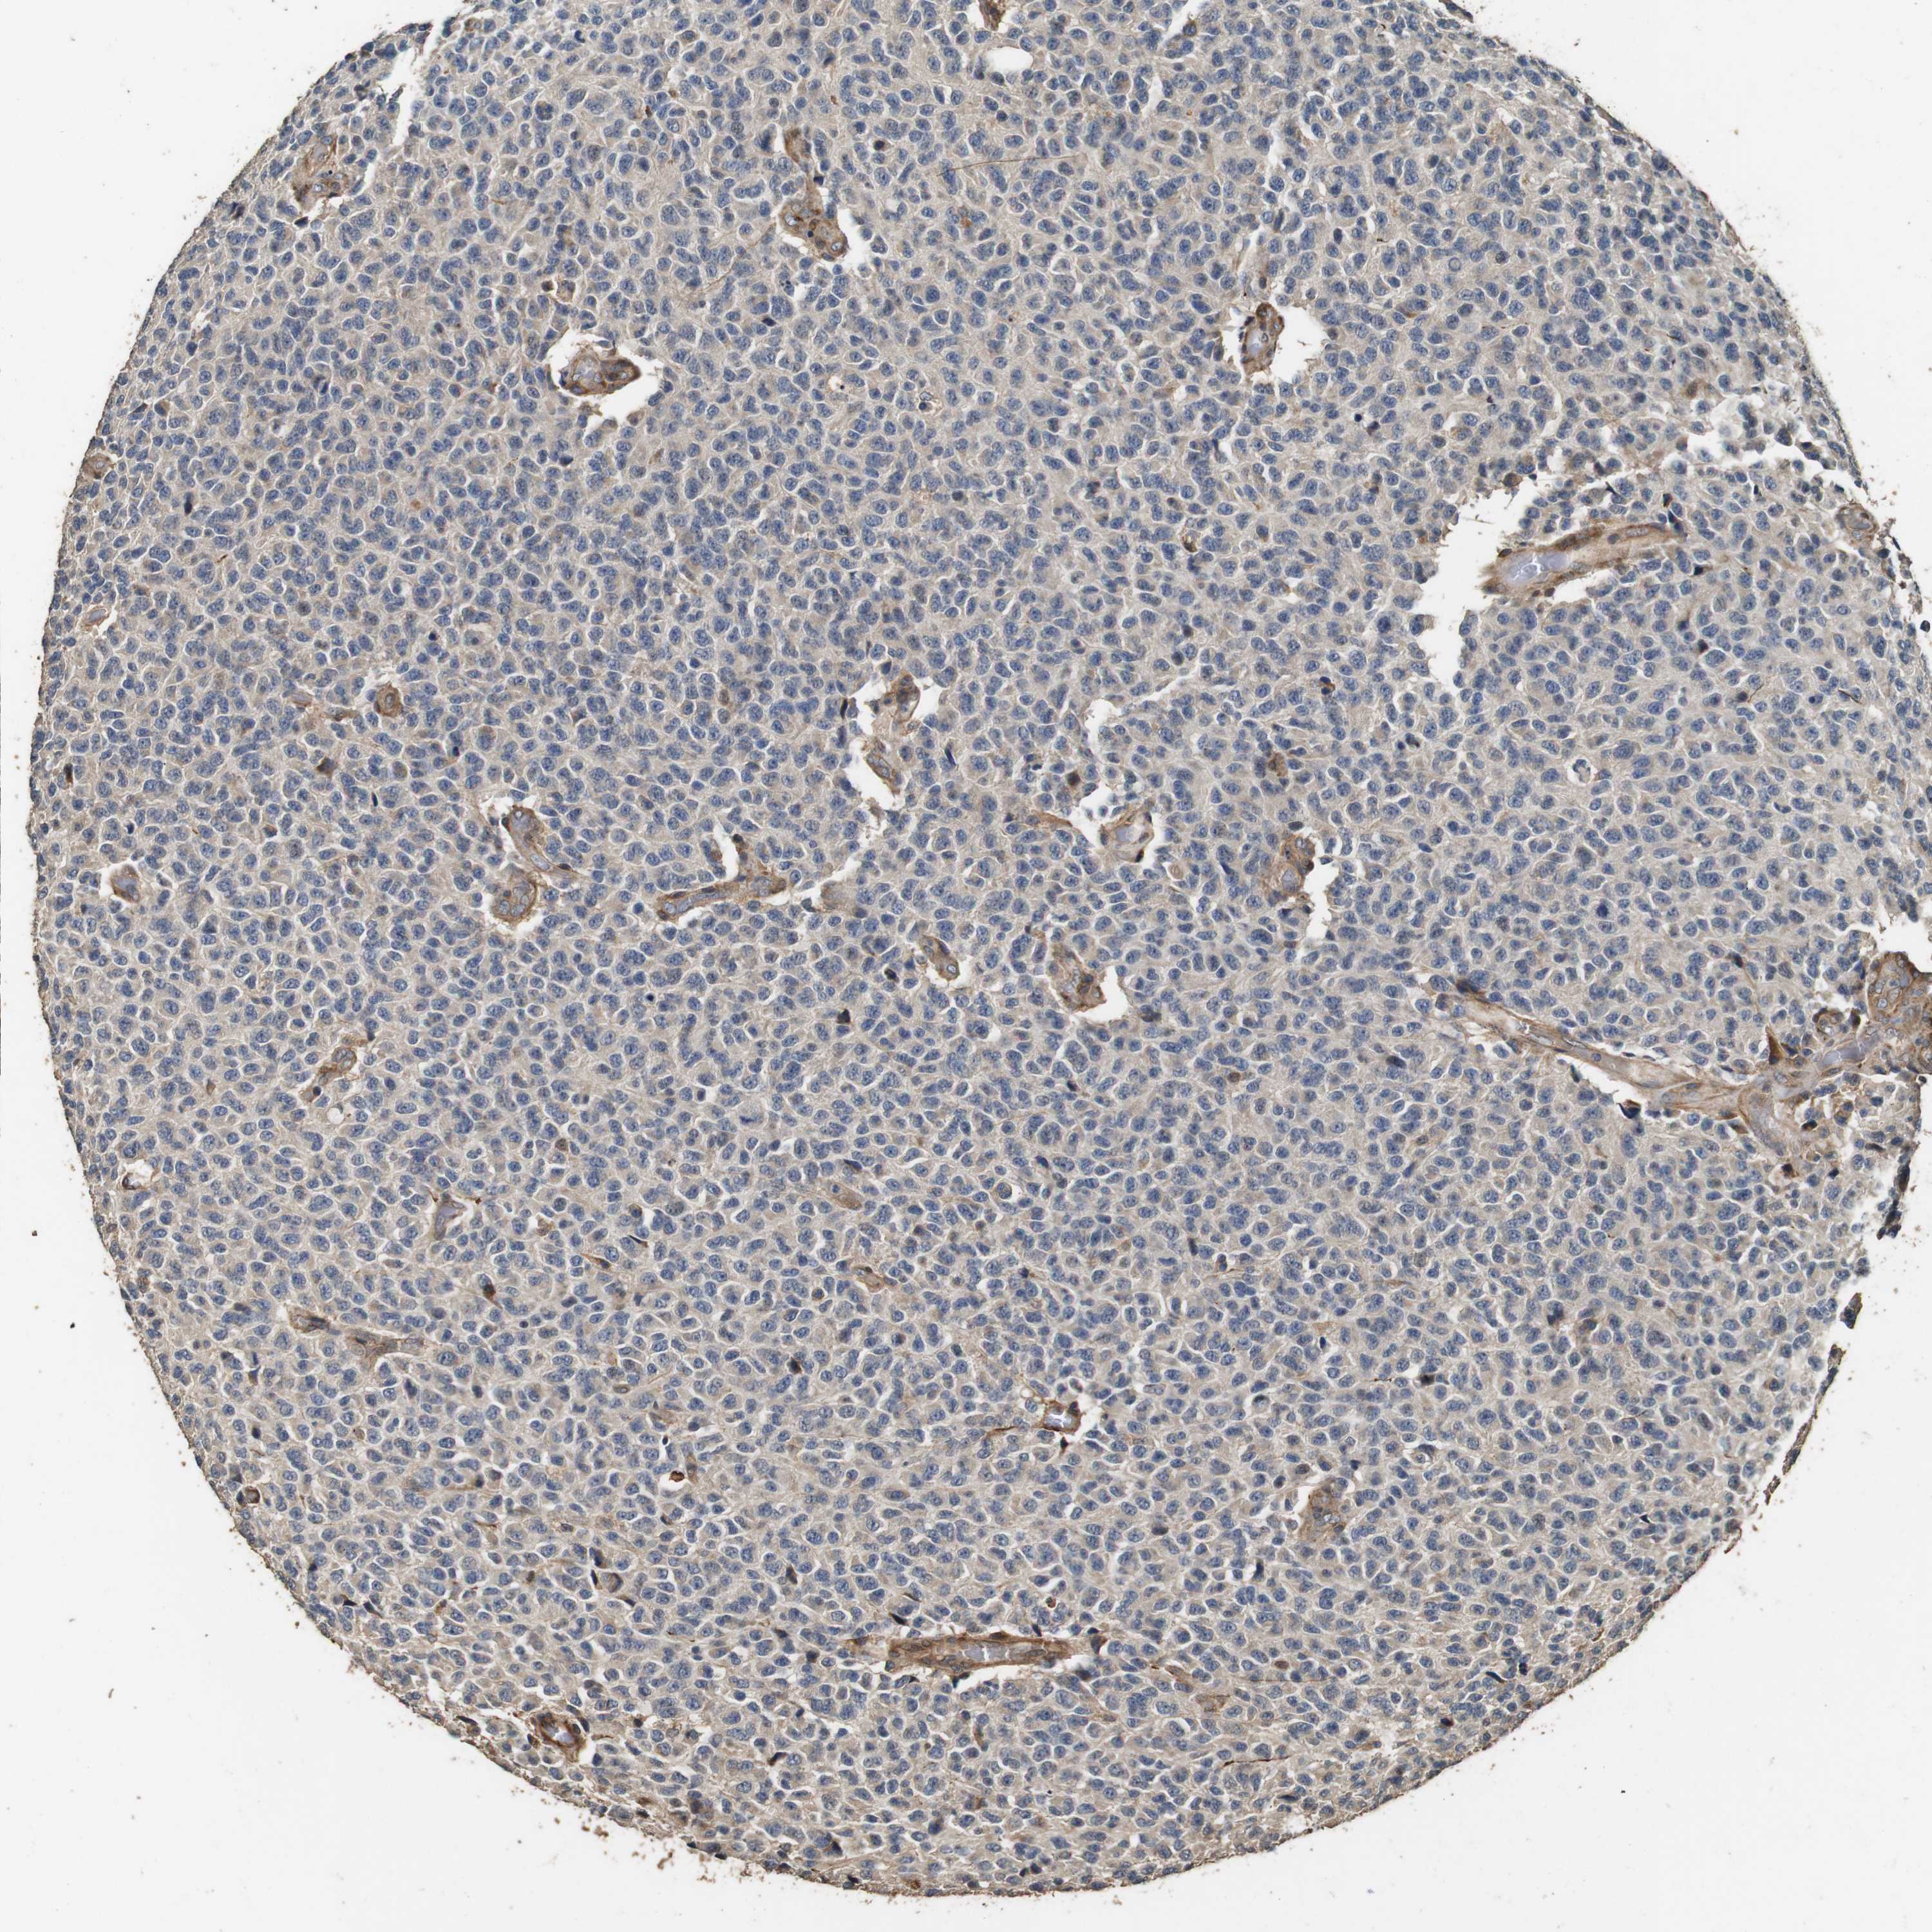

GLIOMA - Protein expressioni

A mouse-over function shows sample information and annotation data. Click on an image to view it in a full screen mode. Samples can be filtered based on level of antibody staining by selecting one or several of the following categories: high, medium, low and not detected. The assay and annotation is described here.

Note that samples used for immunohistochemistry by the Human Protein Atlas do not correspond to samples in the TCGA dataset.

Antibody stainingi

Antibody staining in the annotated cell types in the current human tissue is reported as not detected, low, medium, or high, based on conventional immunohistochemistry profiling in selected tissues. This score is based on the combination of the staining intensity and fraction of stained cells.

Each image is clickable and will lead to virtual microscopy that enables deeper exploration of all samples and also displays staining intensity scores, fraction scores and subcellular localization as well as patient and tissue information for each sample.

Antibody HPA014166

Antibody HPA025240

Staining

High

Medium

Low

Not detected

Intensity

Strong

Moderate

Weak

Negative

Quantity

>75%

75%-25%

<25%

None

Location

Nuclear

Cytoplasmic/membranous

Cytoplasmic/membranous,nuclear

Glioma, malignant, High grade

Glioma, malignant, Low grade